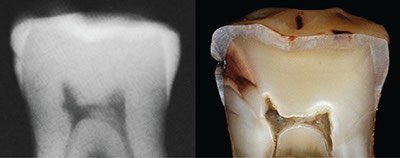

٣/التسوسات ما بين الأسنان:

هذه التسوسات عادة تحدث اذا لم تستخدم الخيط السني بإنتظام..وهذا النوع "الخفي" من التسوس يحتاج اكتشاف مبكر عن طريق أشعة من نوع خاص(الصورة ١)وتعمل هذه الأشعة عادة كل ٦ أشهر خلال الفحص الدوري.. الصورة ٢: مقطع عرضي لتسوس مايين الأسنان

٤/الاشعة الصغيرة:

هذا ما تكشف عنه اشعة الأسنان الصغيرة: التسوسات في الأسطح الملساء او الأسطح ما بين الأسنان والتي لا يمكن كشفها بالعين خلال الفحص.. خاصة اذا كانت اسنانك متلاصقة (الطبيعي) يجب عمل هذه الأشعة خلال الكشف الدوري وكل ٦ اشهر